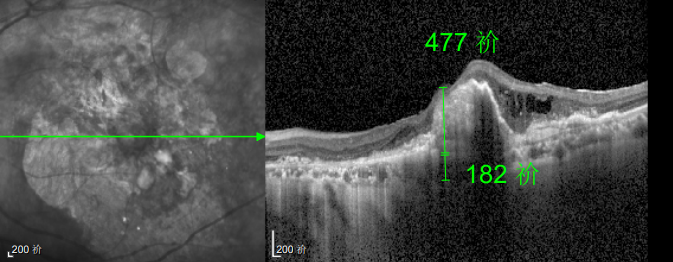

然而好景不长,半年后林婆婆的左眼视力突然骤降,甚至连眼前的人影都难以看清。但她仍抱有侥幸心理,觉得 “再打一针就能好”,恰逢春节临近,便把复查的事一推再推,又延误了3个多月才匆匆赶回医院,可检查结果却给了她沉重一击:由于病情延误,持续的积液已造成黄斑的不可逆损坏,即便后续恢复治疗,也难以回到理想水平。“当时真是肠子都悔青了!”回忆起这段经历,林婆婆至今仍难掩懊悔。

幸运的是,三年后的一次例行复查中,医生通过眼底监测及时发现林婆婆的右眼眼底病变问题,确诊为湿性老年性黄斑变性。得益于定期筛查的及时性,王晓波主任第一时间为她启动治疗,最终成功将右眼矫正视力稳定在0.8左右。